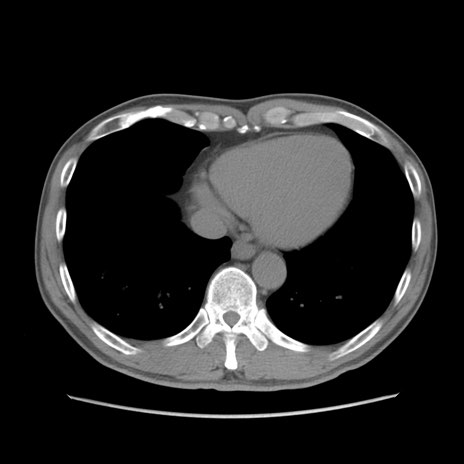

症例56 CT(横断像)